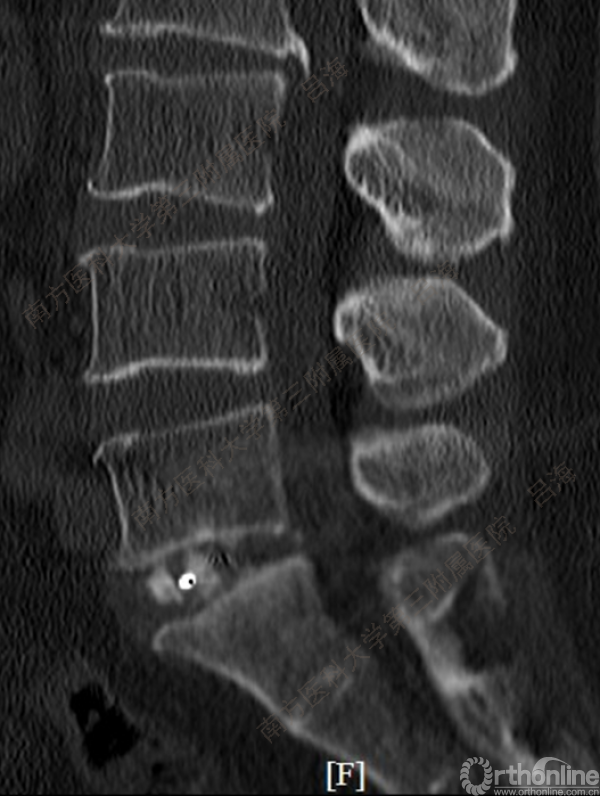

随着社会老龄化进程加快,胸腰椎退行性病变的治疗已经成为脊柱学术界的一个热点话题。MIS-TLIF手术可以治疗多种不同的胸腰椎退行性疾病,南方医科大学第三附属医院吕海教授结合病例为我们一一展示了该术式在治疗不同胸腰椎疾病时的具体手术过程。